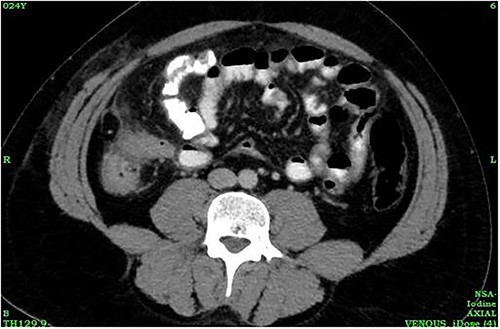

A 24-year-old male was admitted to the General Surgery out-patients clinic with a 2-week history of right iliac fossa pain. The patient had no other associated gastrointestinal symptoms. He had no other significant medical history but had undergone an open appendectomy for perforated appendicitis three months prior to the current presentation. Patient was vitally stable on presentation and the per abdominal examination showed tenderness at the McBurney’s point. A computed tomography (CT) scan of the abdomen revealed thickened and enhanced stump appendix along with adjacent fat stranding and multiple mesenteric nodes; suggestive of SA (Fig. 1). There was also a suggestion of adhesions and mild wall thickening of adjacent caecal wall with no evidence of collections or bowel mass (Fig. 2). Considering the upward trend seen in white blood cell count and the CT report, we planned the patient for a diagnostic laparoscopy. Pre-anaesthesia clearance was obtained.